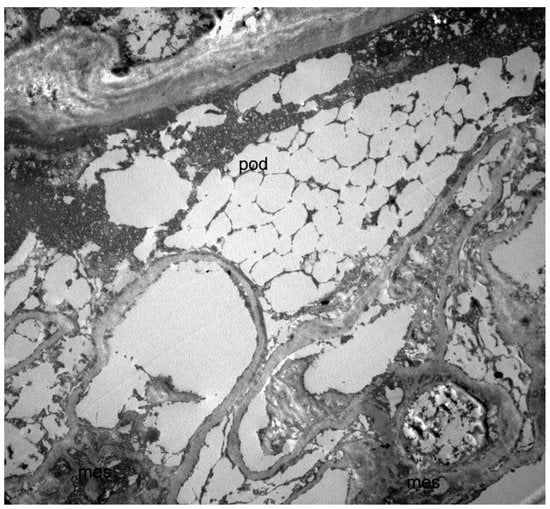

To confirm the kidney disease etiology, we recently analyzed the residual material from the native kidney biopsy by electron microscopy, finding abundant electron-lucent microvacuoles in many cell types and multivacuolized appearance of podocytes (Figure 2).

The histological hallmark of Fabry nephropathy in the N215S variant seems to be the lysosomal glycosphingolipid deposition almost exclusively within podocytes, explaining the possible presence of proteinuria without relevant kidney disfunction. Conversely, accumulation in men with the classic phenotype is detected in several renal cell types, including podocytes, mesangium, vascular endothelium, smooth muscle cells, and interstitial cells [12,13]. Interestingly, in our case, signs compatible with glycosphingolipid storage were detected in podocytes and many other renal cells, possibly explaining the atypical clinical presentation with the advanced renal disease at a relatively earlier age compared to the literature.

The presence of renal failure associated with concentric LVH should have raised suspicion of Fabry disease. As it often happens for rare diseases, it is crucial to point out the diagnostic delay. In this patient, the diagnosis was made eight years after the detection of proteinuria and kidney biopsy. Thus, we can assume that the diagnostic delay is even longer, consistently with the literature [14]. Electron microscopy (EM) was not performed at the time of biopsy, and the findings at light microscopy were interpreted as nephroangiosclerosis in a patient with hypertension. Although limited by the specimen storage conditions, findings from a retrospective overhauling of the residual material from the native kidney biopsy by EM are compatible with the kidney involvement of Fabry disease. Of note, when performing a kidney biopsy in the presence of signs and symptoms consistent with Fabry disease, EM is recommended together with light microscopy.

Figure 2. Transmission electron microscopy image of the kidney biopsy (10 × 3000), showing a multivacuolized appearance of a podocyte (pod). Since the analysis in electron microscopy was carried out on a fragment of renal tissue recovered from paraffin (and not on a standard glutaraldehyde fixed preparation), the overall structural detail was poorly preserved, and glycosphingolipid deposits could not be directly visualized due to the extraction of the lipid components. This resulted in a multivacuolized appearance of the podocytes that, although not strictly diagnostic, was compatible with the diagnosis of Fabry disease.